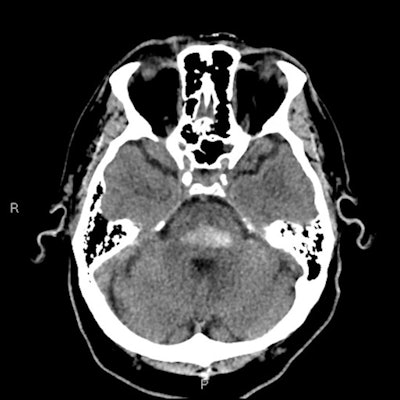

Hypoxic brain injury is an unfortunate consequence of drug addiction and especially drug overdose. Any illegal drugs are central nervous system (CNS) depressants, and overdose can lead to respiratory depression, respiratory arrest, and subsequent hypoxia. The early findings in CT are those of cerebral edema. Some drugs such as heroin have a vasospastic effect that can produce focal infarcts, and for those who survive the event, the long-term appearances are varying degrees of cerebral atrophy, the researchers explained.

"Cocaine causes cerebral vasospasm, and significantly reduces cerebral blood flow," they pointed out. "Cocaine abuse is also associated with both parenchymal and subarachnoid hemorrhage, which are twice as common as ischemic events."

Amphetamines are synthetic psychostimulant drugs. Methamphetamine is generally swallowed, injected, or smoked, but it can also be inhaled, the researchers explained. The most potent form is "crystal meth" or "ice." Amphetamines cause vasoconstriction and increased cardiac output, which can lead to severe hypertension; this is one of the leading causes of cerebral hemorrhage in meth users.